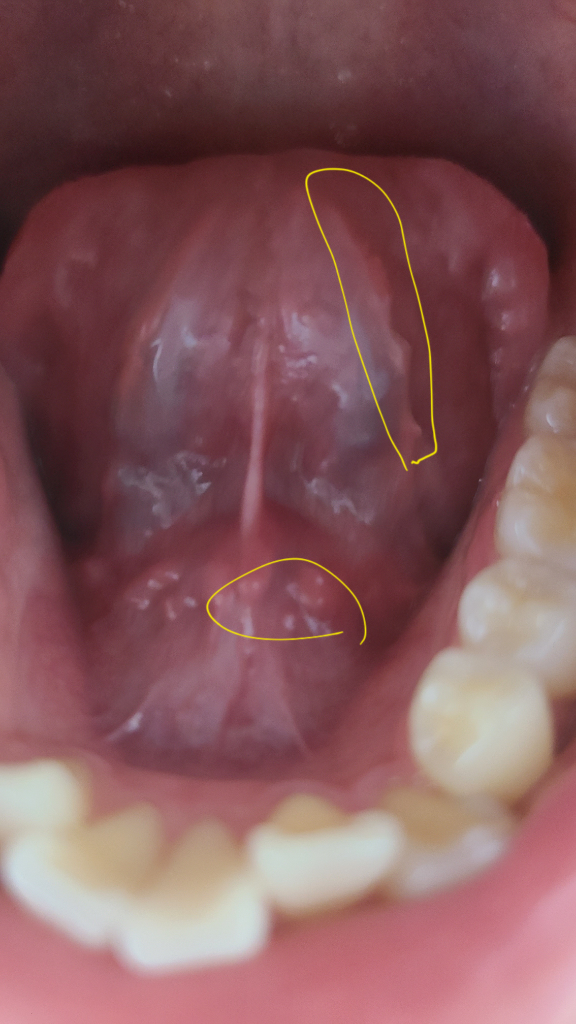

혀 밑에 이것들은 괜찮은 건가요?

오늘 혀 밑을 보니 뭔가 우둘투둘해서요.. 딱히 불편한 느낌은 없는데 정상적인 구조물들인가요?? 혹시 침샘에 문제가 생긴 건 아닌지 여쭙고 싶습니다 ㅠㅠ

• 안녕하세요. 채홍석 의사입니다. 혀 아래쪽에는 원래 울퉁불퉁한 부분이 있습니다. 침샘입구 혹은 혈관등이 지나가기 때문입니다.

정상적인 구조물이고 염증 등의 이상소견이 보이지 않습니다. 불편감이 없으시다면 그냥 지내셔도 괜찮습니다.